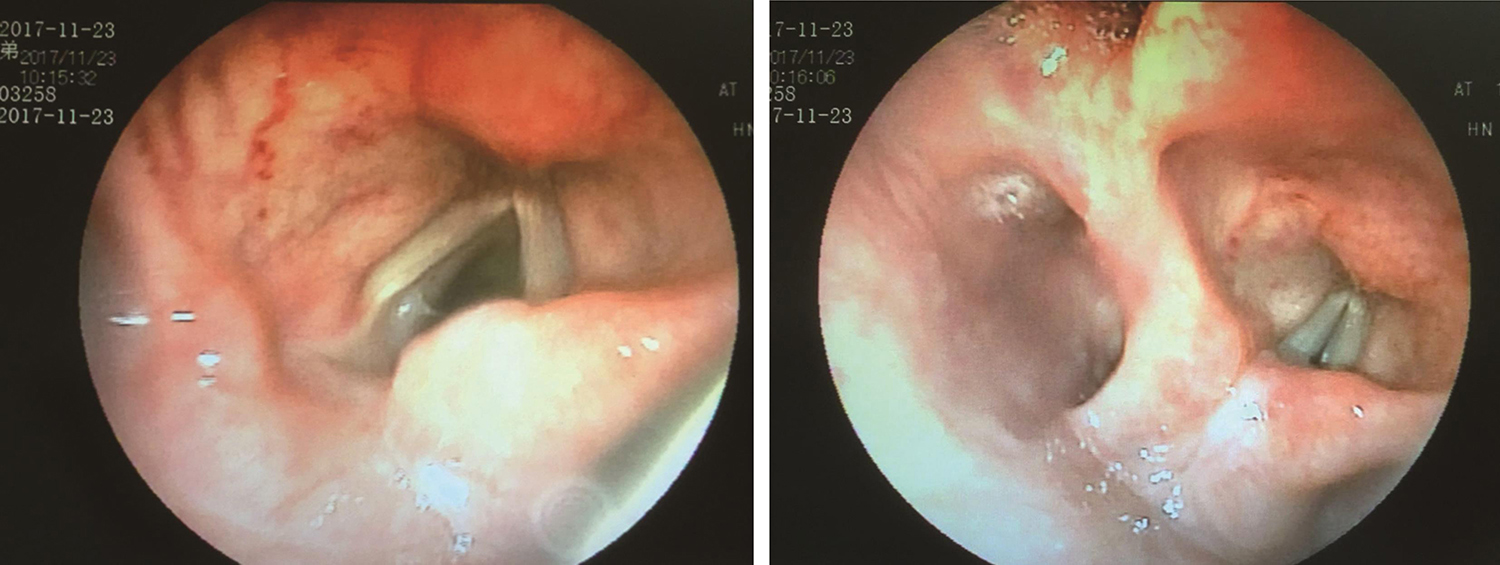

3.2017年8月10日电子喉镜

右侧声带固定于旁正中位,闭合时有裂隙(图5,图6)。

图5 喉镜示右侧声带固定于旁正中位

图6 喉镜示声带闭合时裂隙

2.电子喉镜检查

(2)2017年11月23日:右侧声带位于旁正中位,轻微活动,声带闭合时有裂隙(图14)。

图14 2017年11月23日复查喉镜